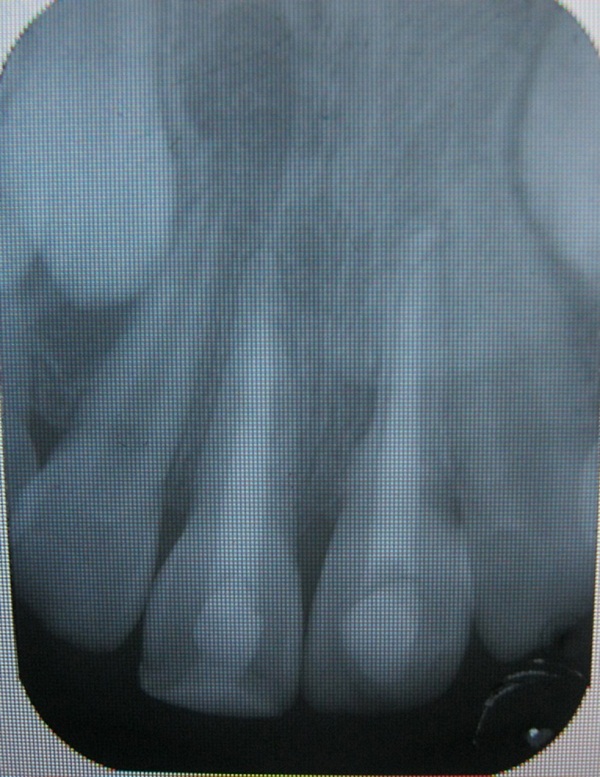

Foto 2023 Espacio Del Ligamento Periodontal

Se observa ensanchamiento del espacio del ligamento periodontal de... | Download Scientific Diagram

Pza.13,14 y15. Ensanchamiento del espacio para el ligamento... | Download Scientific Diagram